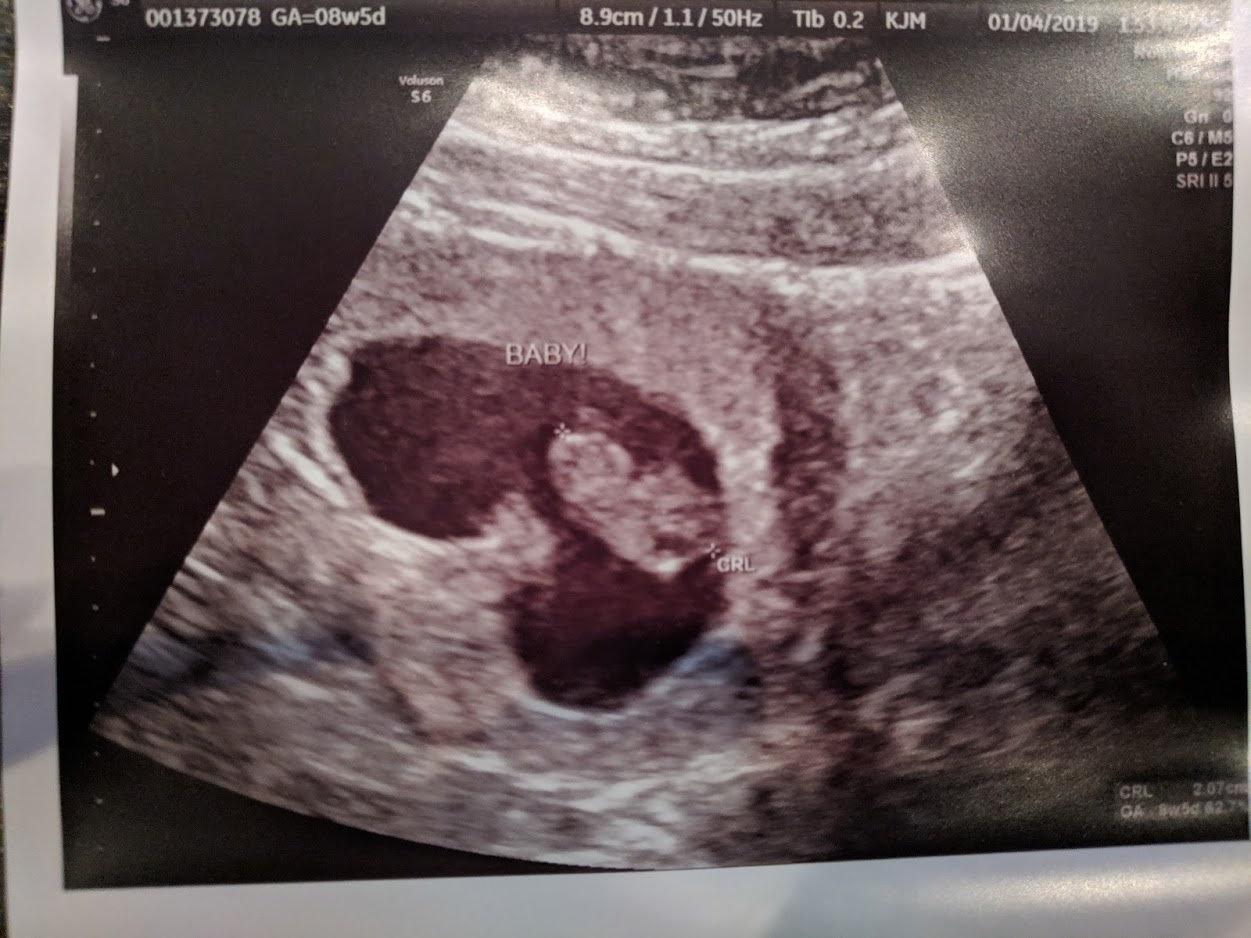

8w3d today. I completely freaked out thinking there would be awful news. I sat there praying in agony because I truly don't think I have another IVF in me. My ass is sore and numb from the shots. When I heard his heart beat (185), all of my fears, in that moment, melted away. Complete awe is the only way to describe it. All I wanted to do was listen to it forever. My rainbow. My little boy. I have a little baby. I'm someone's Mother